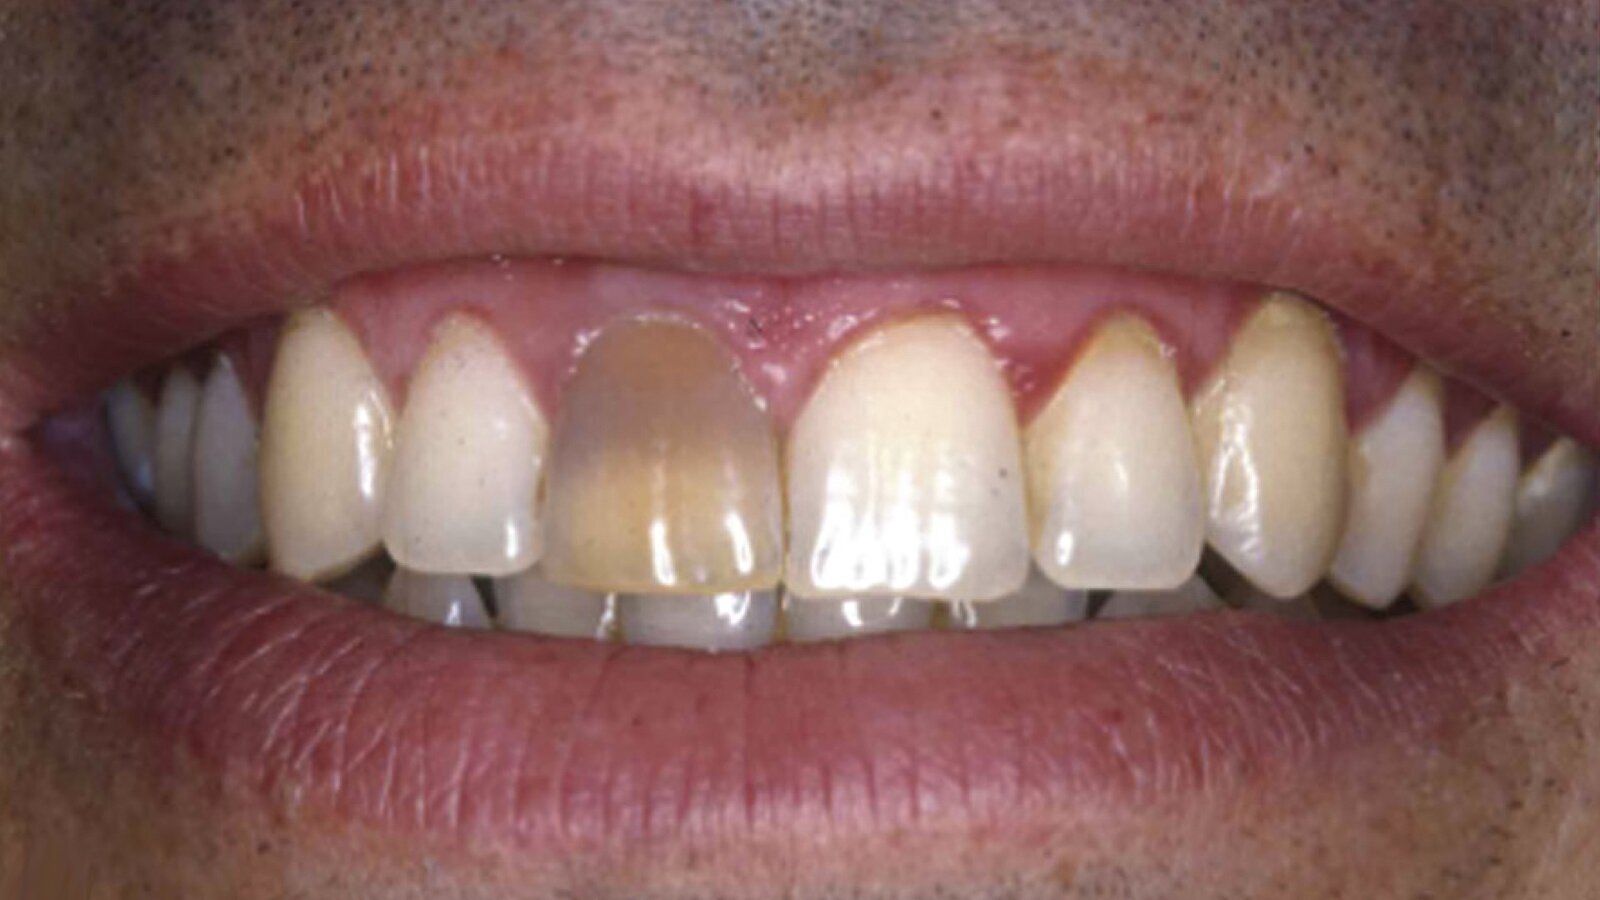

Figura 2A. Preoperatorio: cambio de coloración en la pieza 21 por residuos de obturaciones de tratamiento endodóntico anterior, donde se observan también restauraciones con resinas filtradas y restos de cálculo por higiene bucal deficiente.

Figura 2B. Postoperatorio luego del blanqueamiento interno y externo ambulatorio y el cambio de las restauraciones de resina filtradas.